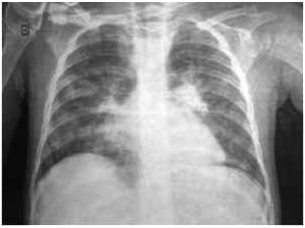

Paciente do sexo feminino, de 65 anos, portadora de hipertensão arterial e dislipidemia mista, chega à sala de emergência com história de dor torácica há três horas, sem fatores de piora. Nega irradiação. Realizou eletrocardiograma mostrado a

seguir, com troponina ultrassensível elevada: